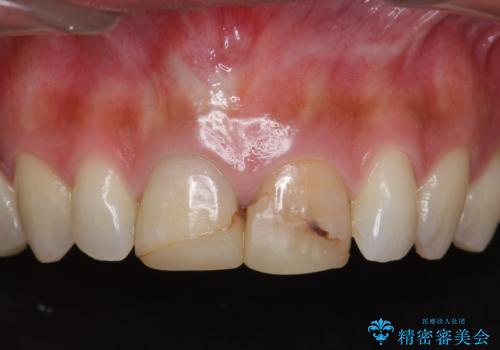

![[ 前歯が割れた ] ブリッジによる審美回復治療の症例 治療前](https://seimitsushinbi.jp/wp/wp-content/uploads/2019/11/603d9508dc3fe40b5437057dd45cc165-500x350.jpg?v=1574859330)